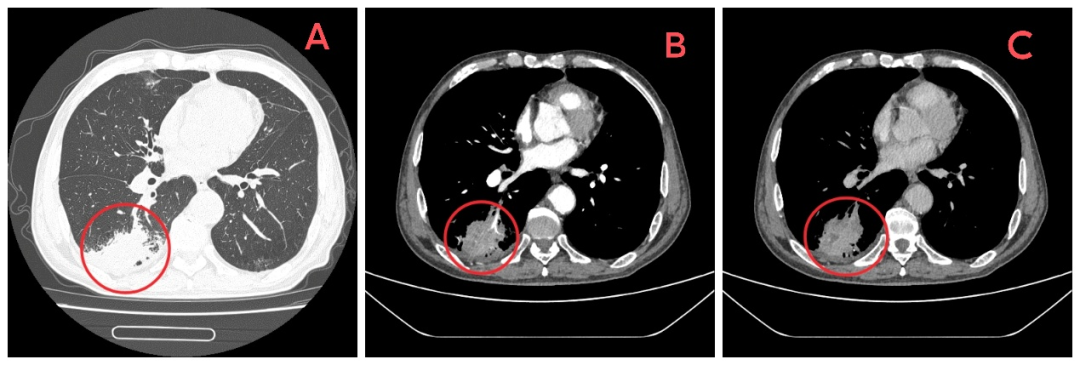

图A:患者胸部平扫CT;图B、C:患者胸部增强CT。红圈标注病变位置。

而住院期间的一次常规胸部CT检查,让所有人的心顿时揪了起来——报告显示,他的右肺下叶靠近胸膜处有一个占位性病变。

更令人焦虑的是,刘大爷的家人带着CT片子咨询了多家医院,几位医生看过影像后都皱眉表示:“这个病灶的形态不太好,需要高度警惕,首先要排除肺癌。”一时间,对疾病担忧的阴霾笼罩了整个家庭。